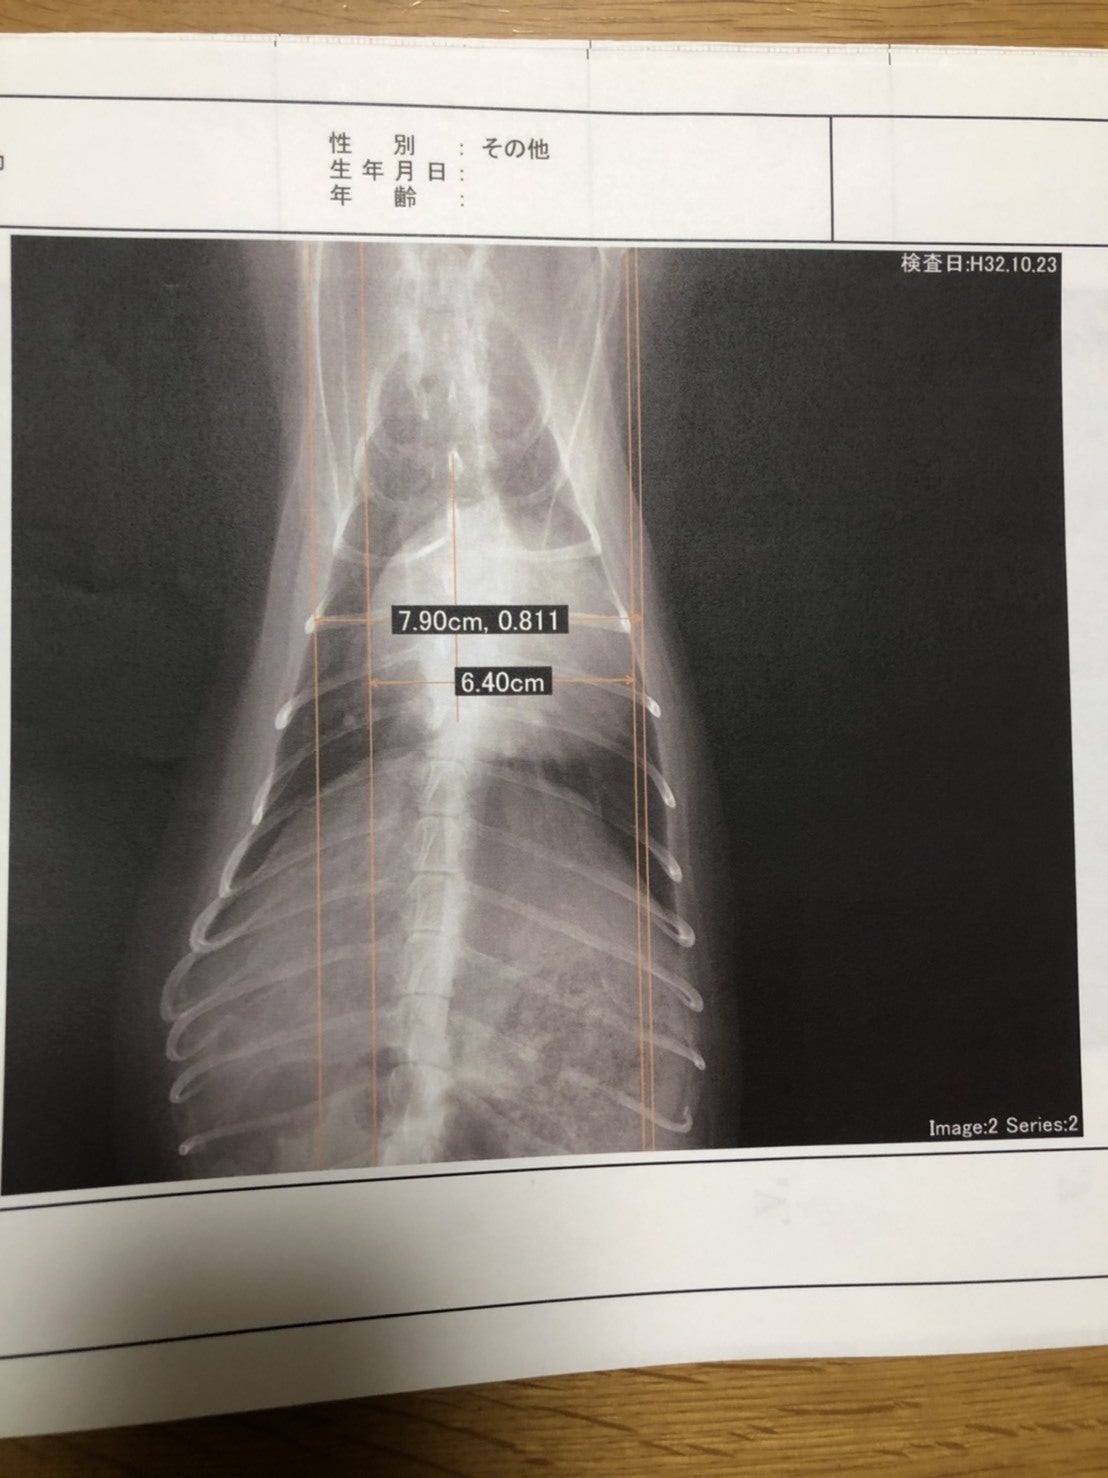

心拡大が認められる

レントゲンでは正常60%未満の心胸比が81.1%で心拡大が認められる。心拡大があり、気道を圧迫しているとのこと